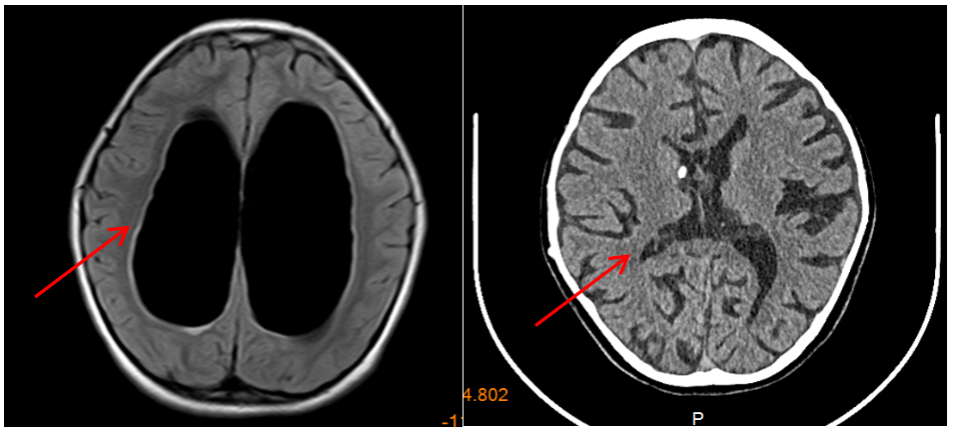

1.小骨窗显微手术:是治疗儿童脑型肺吸虫病的有效方法,具有缩短手术时间,显微镜下顺利寻找病灶边界,减少对周围正常脑组织的牵拉。手术创伤小、恢复周期短,做到对脑组织及周围神经损伤最小。

2.颅脑创伤

·小儿外伤性颅骨凹陷粉碎性骨折

·创伤性硬膜外血肿